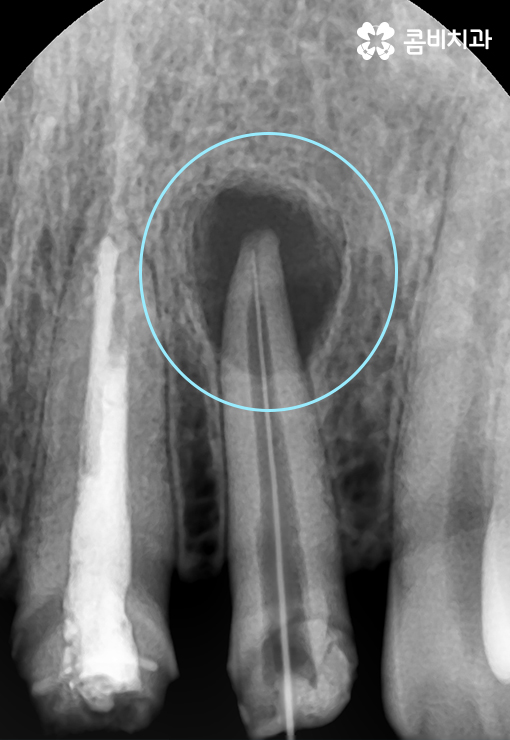

위 엑스레이 사진의 경우 앞니 신경치료 전 상태이며 염증이

치아 뿌리 끝 쪽에 발생하여 신경치료가 필요한 상황입니다.